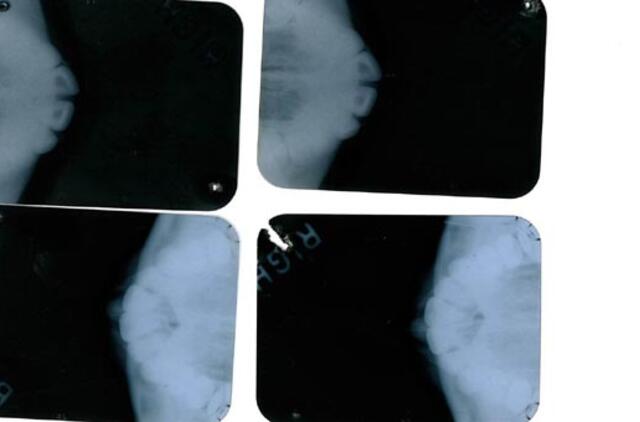

Aukcione Los Andžele sekmadienį parduotos 1962 metais mirusios Holivudo ikonos Merlin Monro (Marilyn Monroe) rentgeno nuotraukos ir medicininių diagnozių pažymos. Nežinomas asmuo už tai paklojo 25 600 dolerių. Aukcionų namai tikėjosi iki 30 000 dolerių.

Dokumentai vienareikšmiškai įrodo, kad aktorei buvo atliktos plastinės operacijos, pavyzdžiui, smakro. Pažymose kalbama apie smakro implantą, kuris pradėjo pamažu irti.